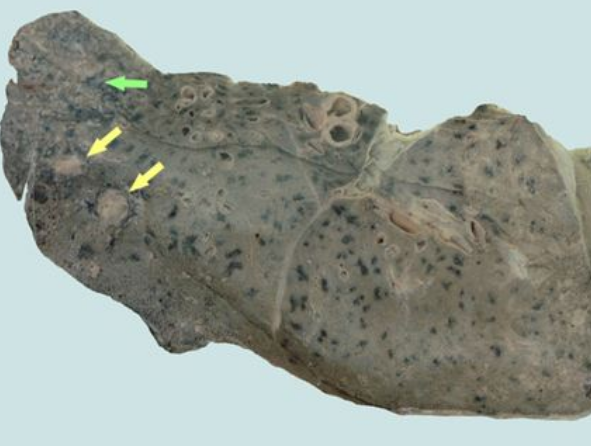

肺結核圖片

A:空洞型肺結核是指病灶中有空洞的肺結核,同樣屬於繼發性肺結核。治療的方法通常依據是初治空洞型肺結核,還是慢性纖維空洞型肺結核,併兼顧患者的臨床症狀與體徵,是否有咯血、混合感染、支氣管播散,或者肺組織受到破壞、毀損等嚴重程度,治療方法不完全相同……